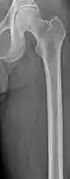

The diagnostic examination of a person with suspected multiple myeloma typically includes a skeletal survey. This is a series of X-rays of the skull, axial skeleton, and proximal long bones. Myeloma activity sometimes appears as "lytic lesions" (with local disappearance of normal bone due to resorption). And on the skull X-ray as "punched-out lesions" (pepper-pot skull). Lesions may also be sclerotic, which is seen as radiodense.[47] Overall, the radiodensity of myeloma is between −30 and 120 Hounsfield units (HU).[48] Magnetic resonance imaging is more sensitive than simple X-rays in the detection of lytic lesions, and may supersede a skeletal survey, especially when vertebral disease is suspected. Occasionally, a CT scan is performed to measure the size of soft-tissue plasmacytomas. Bone scans are typically not of any additional value in the workup of people with myeloma (no new bone formation; lytic lesions not well visualized on bone scan).

Femur with multiple myeloma lesions

Same femur before myeloma lesions for comparison